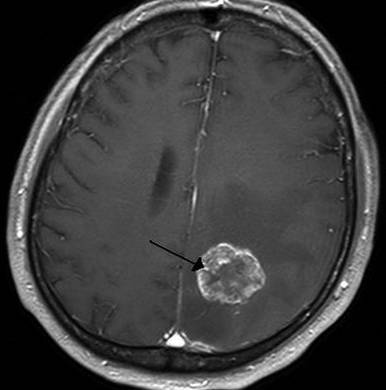

Ключевая роль в неврологической диагностике мозговых опухолей принадлежит рентгенографии, а также компьютерной и магнитно-резонансной томографиям. Эти методики применяют цифровую обработку результата рентгенологического обследования, что выявляет расположение и форму раковой опухоли.